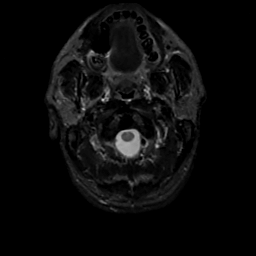

MR Study #8, March 31, 1991 -- Slice #0

[Home][Help][Clinical][Tour 1][Tour 2] Slice 0